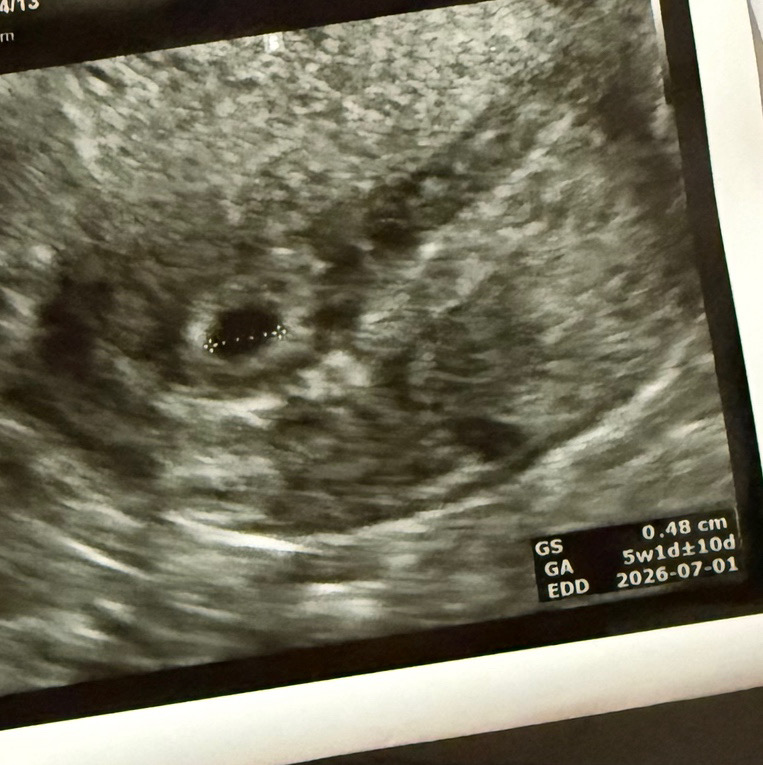

임신 5주차 아기집 크기 괜찮은가요? ㅠㅠ

한번 유산 경험 후 재임신이다보니 혹시나 또 잘못 될까봐 두려워요 ㅠㅠ

임신 딱 5주차때 난황 안보이고 아기집만 봤는데 원장님이 아기집이 좀 작네요~착상된지 얼마 안됐나봐요 하셨었는데 지금 아가 무럭무럭 잘 크고 있어요!(현재 18주 입니다) 착상이 좀 늦어서 아기집이 작을수도 있으니 너무 걱정 마시고 6~7주때 다시 확인하러 가보세요!